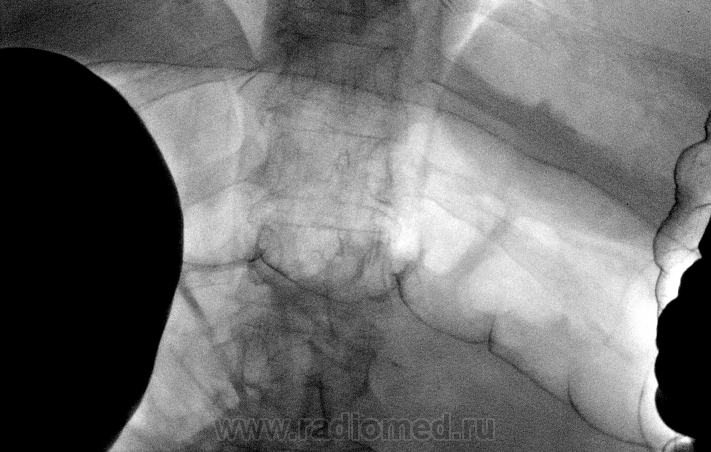

Пациентка 70 лет, направлена на ирригоскопию для исключения органической патологии, предворительно дважды проходила колоноскопию(без патологии), последний раз на кануне проведения исследования.

Снимки восходящий отдела ободочной кишки сделаны в положении на животе и стоя. Ваше мнение?

Последний и предпоследний снимок это восходящий отдел ободочной кишки, а если была бы перистальтика то мы бы увидели на последнем снимке в вертикальном положении законтрастированную слепую кишку.

Да, я предпологаю об инфильтративной форме рака. Эндоскописты только со второго раза так же описали о сужении просвета на 4/5, взяли биоптат, думаю на этой неделе готова будет.

Прекрасная подготовка пациентки к исследованию, мастерское владение методикой первичного двойного контрастирования и как следствие результат.Похоже на рак толстой кишки.

Результат гистологии-аденокарцинома.

Данный снимок сделан на животе Игорь Иванович, отмеченный Вами участок это ещё восходящий отдел, далее я отметил красными стрелками где частично контраст прошол в н/3 восходящего отдела и слепую кишку . поэтому диагноз звучит как рак восходящего отдела ободочной кишки.